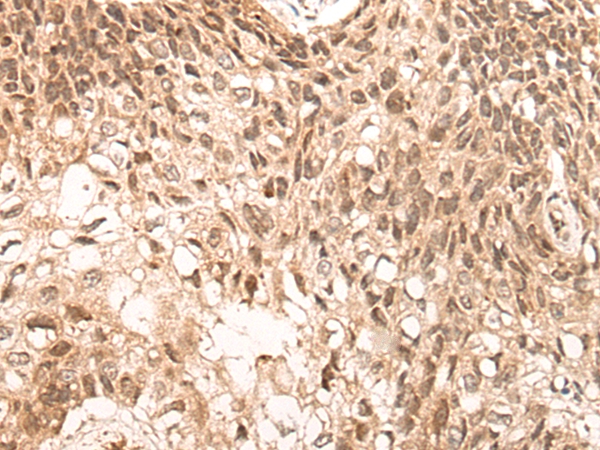

图片:

The image on the left is immunohistochemistry of paraffin-embedded Human lung cancer tissue using 46623(NCOA6 Antibody) at dilution 1/30, on the right is treated with synthetic peptide. (Original magnification: x200)